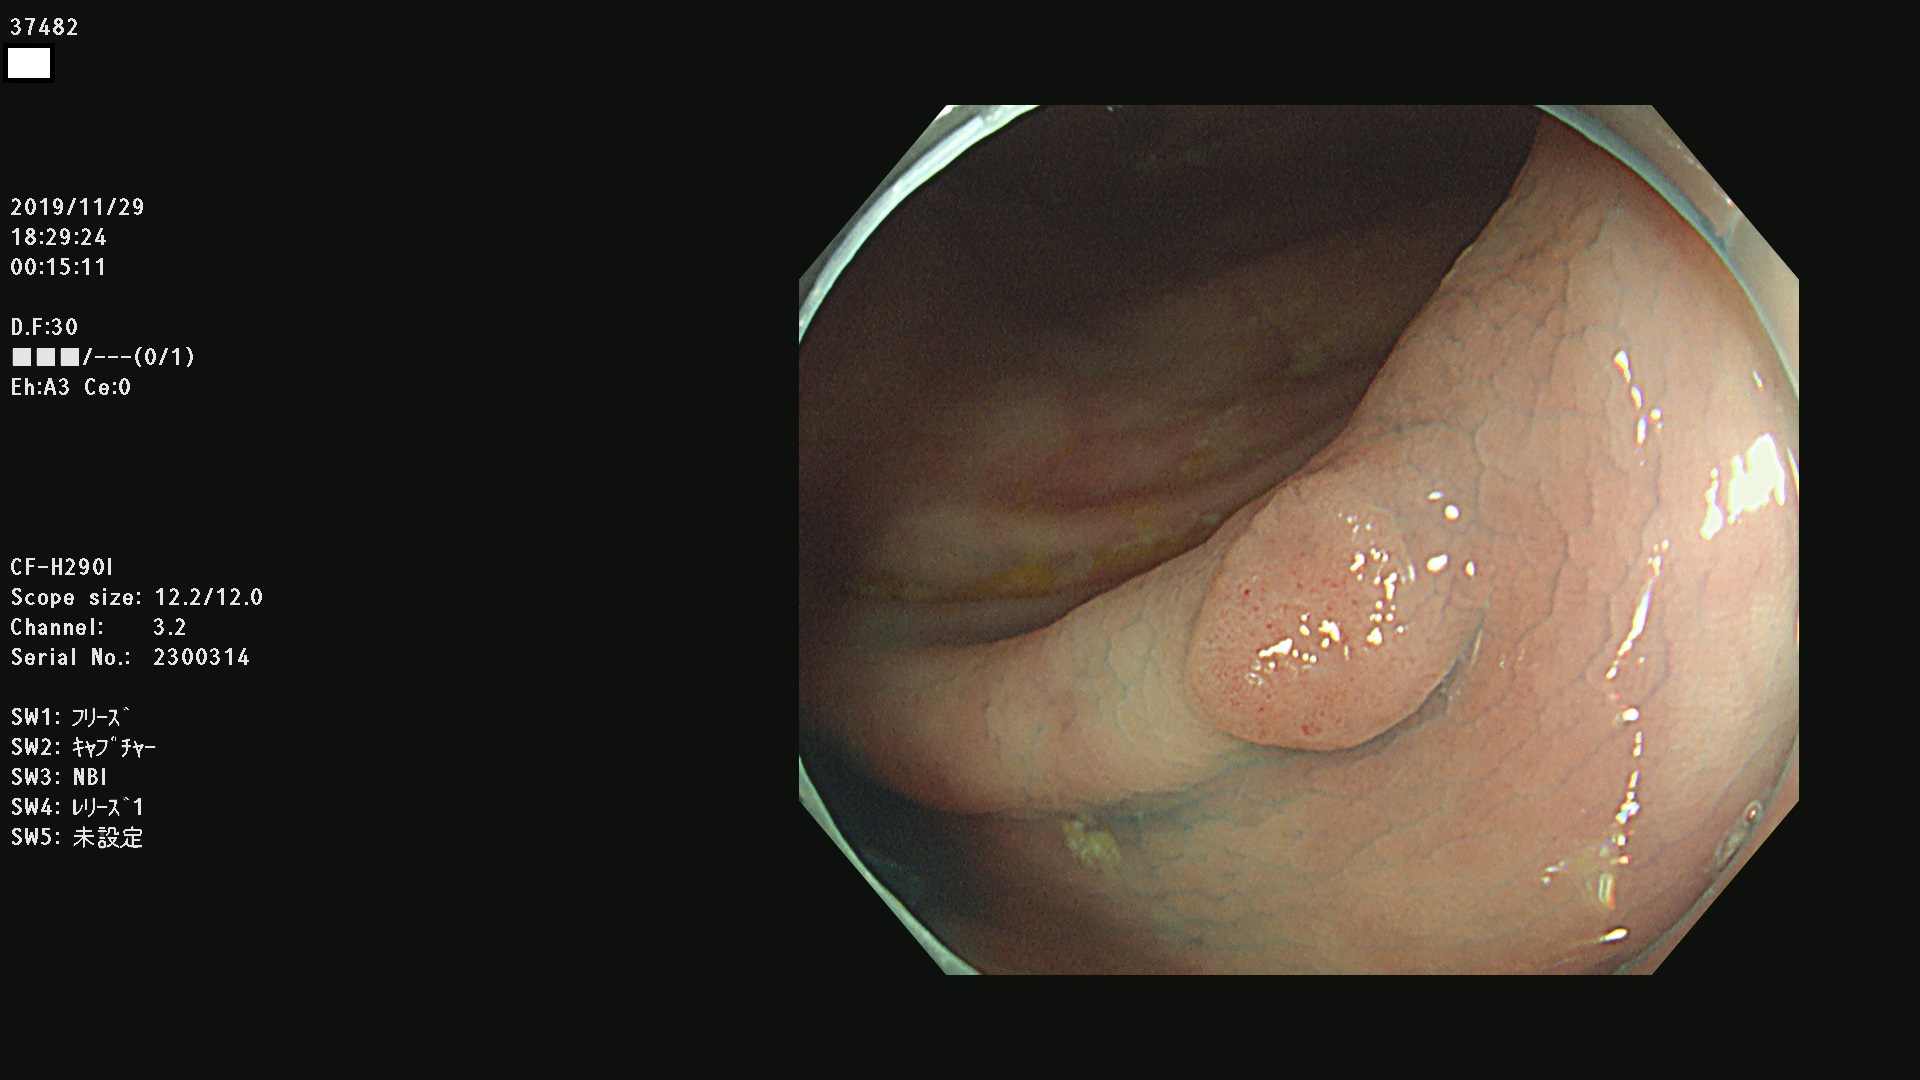

37400(SSAPのみ) 37401 37403 37404 37405 37406 37407 37408 37410 37411 37412 37413 37415 37416 37417 37420 37423 37424 37425 37426 37428 37430(SSAPのみ) 37432 37433 37434 37435 37436 37437 37438 37439 37440 37442 37443 37444 37447 37448 37449 37450 37451 37452 37455 37456 37457 37458 37459 37460 37461 37462 37464 37467 37468 37469 37470(SSAPのみ) 37471 37472 37474 37476(SSAPのみ) 37477 37478 37480 37481 37482 37483 37485 37486 37487 37488 37489 37490 37491 37492 37493 37494 37497 37499

発見困難で危険性の高い平坦型病変(上記100名より抽出)